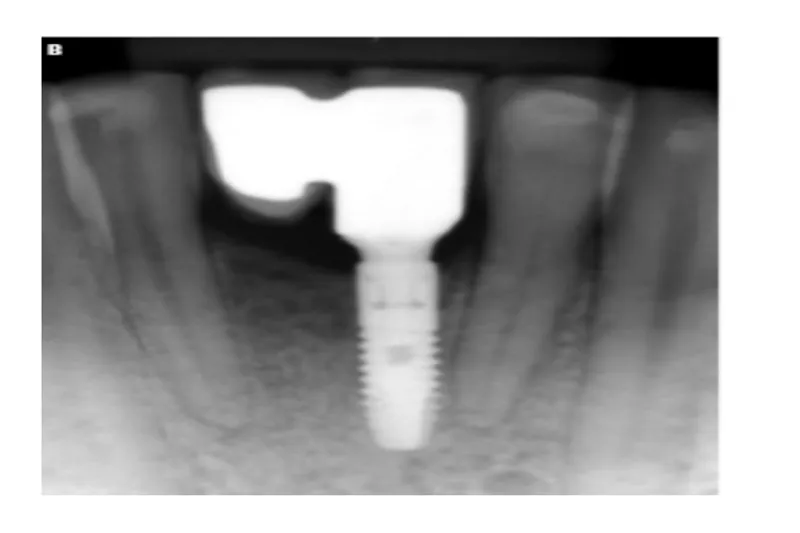

Skal vi fremstille en tandunderstøttet bro eller en implantatunderstøttet erstatning, når en patient har behov for at få erstattet enkelte tænder?

Implantater har som udgangspunkt en dårligere prognose end tænder, men fordelen ved at indsætte implantater som erstatning for mistede tænder på sunde personer er, at nabotænderne skånes og brospandets længde reduceres.

Overlevelsesprognosen for implantatunderstøttede rekonstruktioner synes lige så god som for tandunderstøttede broer, men frekvensen af komplikationer er imidlertid forholdsvis høj.